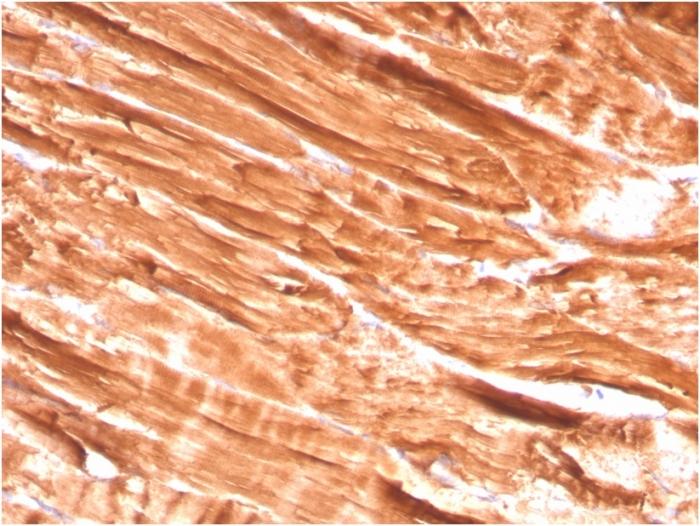

Positive Control

Human skeletal muscle and heart muscle tissues (IHC).

Antibody target cellular localization

Plasma membrane

Cell tissue expression

Muscle